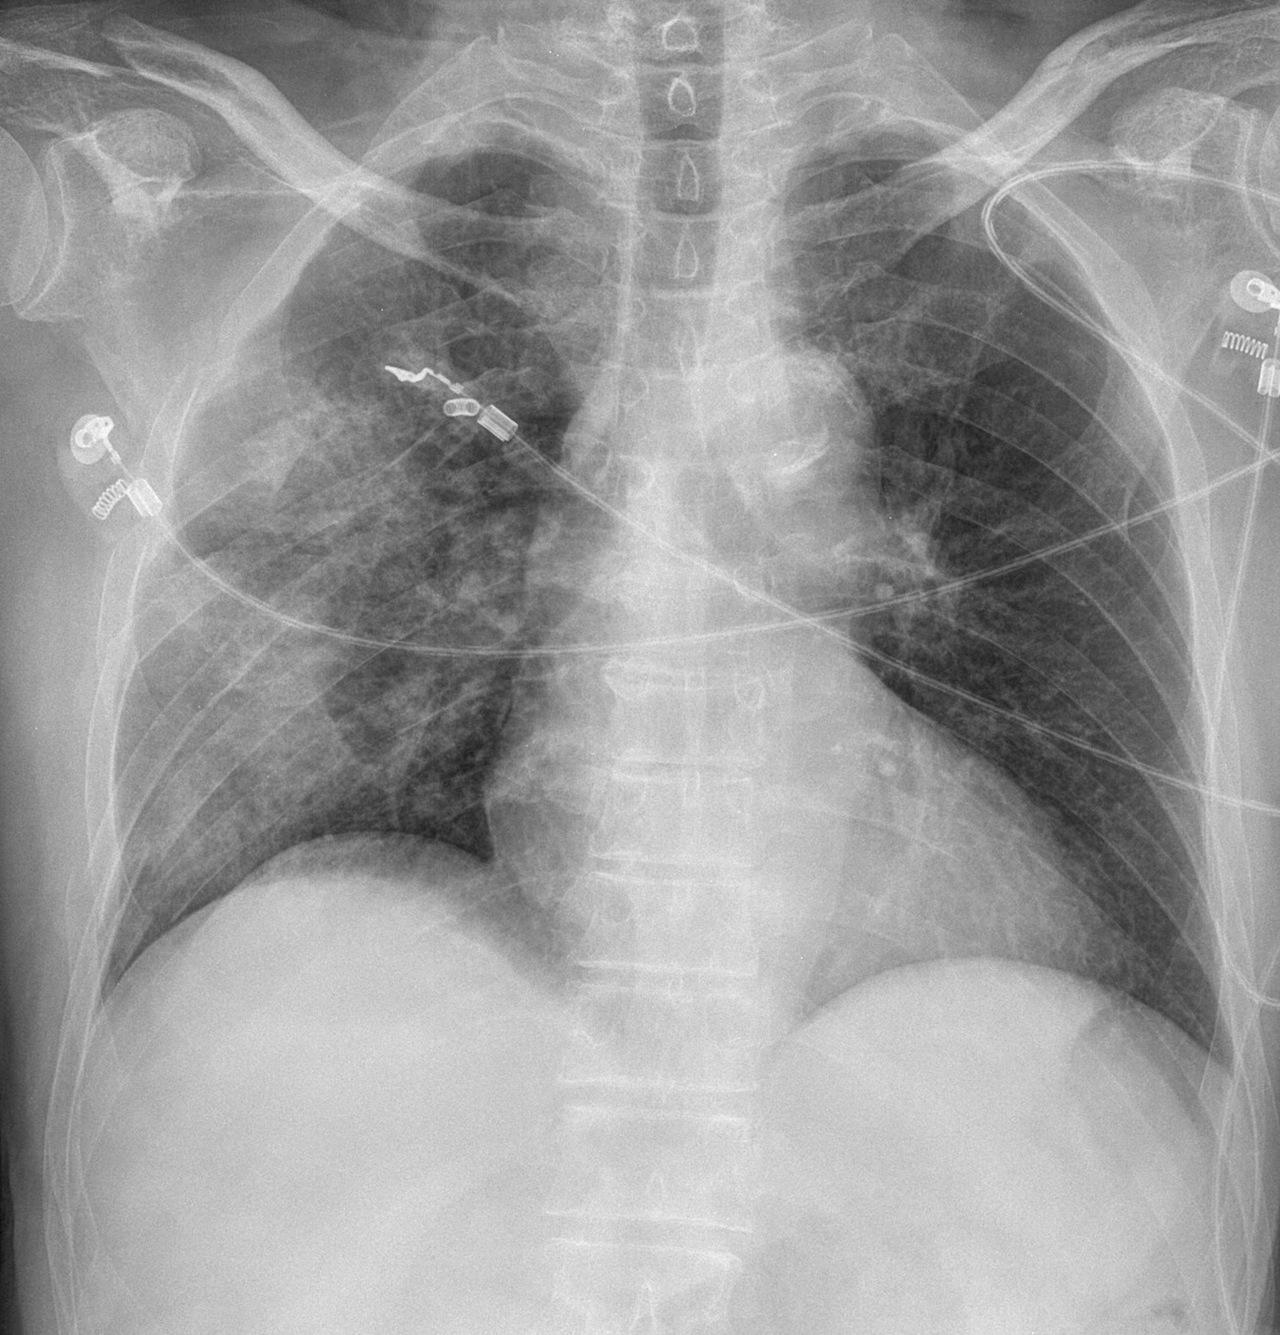

Diaphragm Rupture CXR